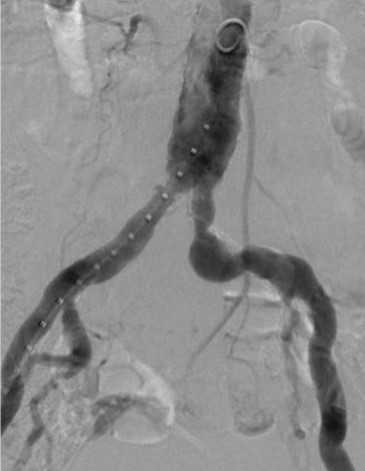

Widely patent arteries demonstrating VBX Stent Graft flexibility and radial strength in a highly tortuous vessel